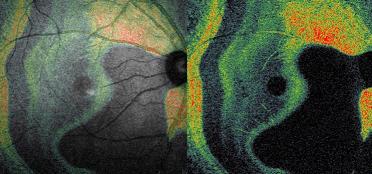

Resim 3: Yandaki resim normal makulanın C-tarama OKT görüntüsüdür. Makulanın normal katlarının mevcut olduğu, herhangi bir sıvı göstergesi olan boşlukların olmadığı izlenmektedir.

Resim 4: Makulada sıvı birikimini (kistik makula ödemi) gösteren C-tarama OKT görüntüsü. Makula ödemi için tipik petek tarzında olan siyah boşluklar izlenmektedir (kırmızı ok).